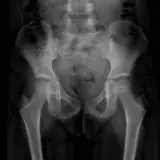

Over 2,100 interactive radiology cases, curated by radiologists for your level of training. Scroll, window, and view cases full screen — just like on PACS. Click linked findings in each writeup to jump straight to them on the image. Cases include sample reports, a focused discussion section, original illustrations, and videos.

Casos totalmente interativos com as ferramentas que você espera em um PACS — rolagem, ajuste de janela, zoom, movimentação, medidas, ROIs e modo de tela cheia.

Casos Interativos

Role, movimente, ajuste janela e amplie como em uma estação PACS do trabalho